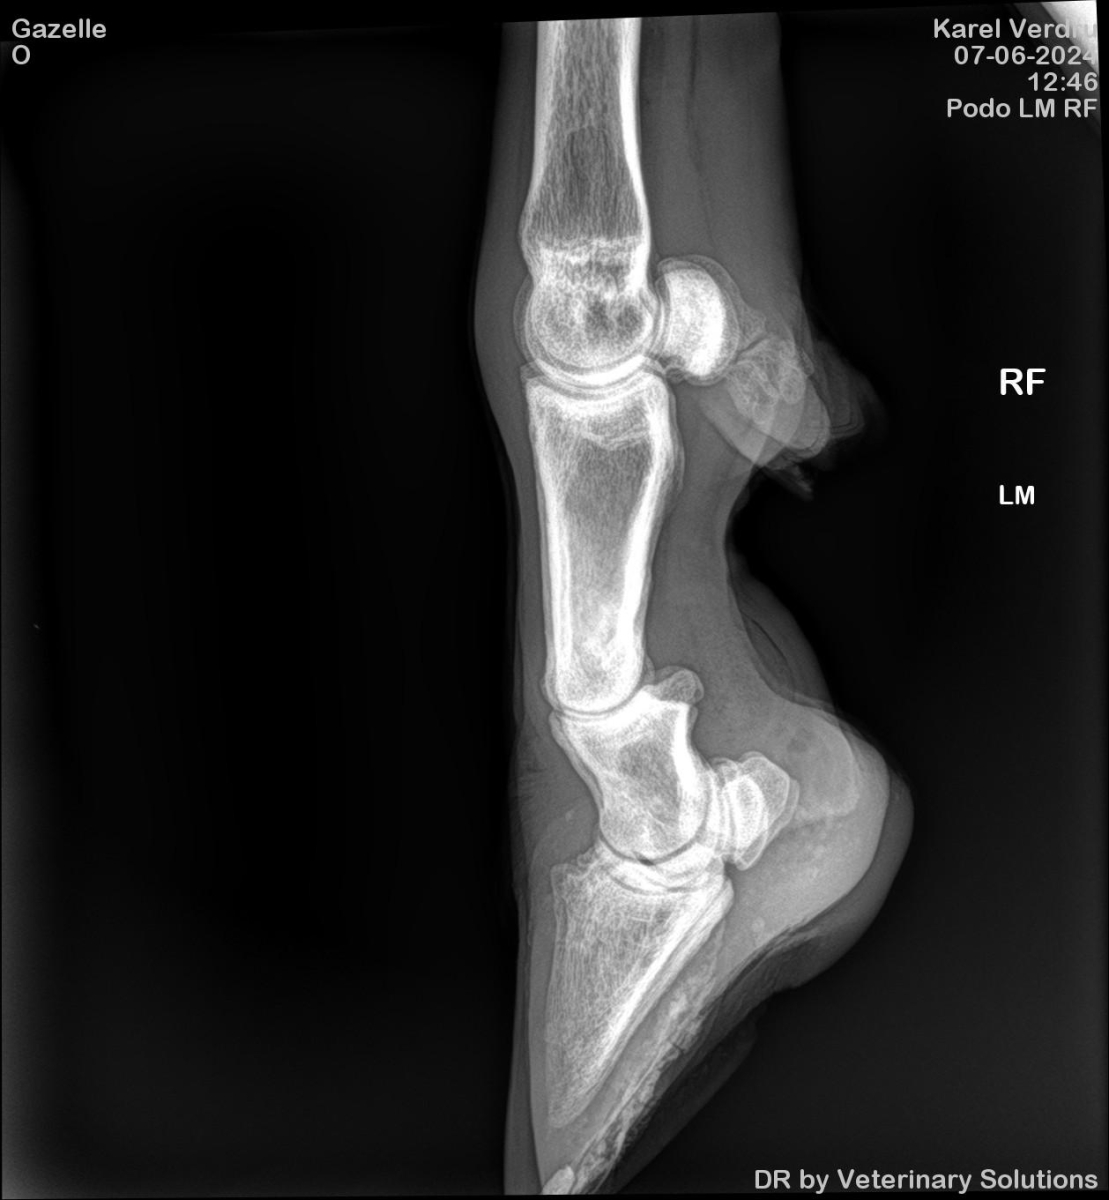

Mankheid-controle bij algazelle Mao

07-06-2024

Algazelle Mao loopt al sinds 17 maart kreupel na het vastzitten in een hooinet. Op 12 april kwam Mao hier ook al ter sprake vanwege de gevoelige wond die hij had opgelopen. Omdat er sprake was van een aanhoudende mankheid werd er besloten om röntgenfoto's te laten nemen zodat we (hopelijk) meer te weten zouden komen over de oorzaak. |

Back-up dierenarts Karel Verdru is langsgekomen om te helpen met zijn draagbare RX-apparaat. In de elleboog van Mao zou er wellicht een probleem zijn met de aanhechting van de spieren. Dit probleem kan de mankheid van Mao verklaren, maar vergt veel tijd en rust om goed aan te helen. We zullen we hem dus vooral veel tijd moeten gunnen.